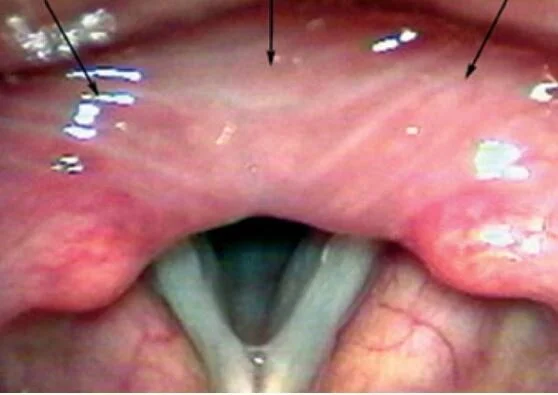

Our patient had bilateral infiltration of the vocal cords with vocal cord paralysis. His presentation was hoarseness which is the reason for 1% of all visits to primary care physicians. Vocal cord paralysis is present in 2.8-8% of the cases. This represents a more serious condition and laryngoscopy is recommended to rule it out.

Edema of the intraarytenoid space may occur as in this case in RA.

In the case of our patient a biopsy was done showing squamous cell carcinoma.